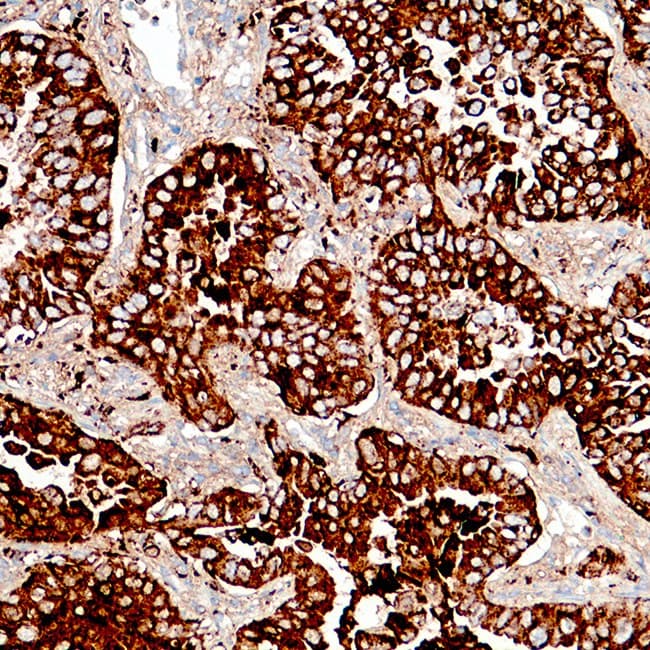

- Detecta una tinción granular citoplasmática asociada con la diferenciación de células alveolares tipo II.

- Utilizados como parte de paneles diagnósticos para la clasificación del adenocarcinoma de pulmón y el diagnóstico diferencial de tumores pulmonares frente a metastásicos.